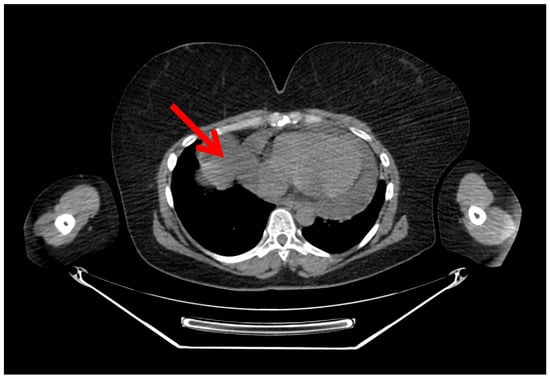

A Rare Case of Multilocular Mesothelial Inclusion Cysts of the Pericardium: Diagnosis, Treatment, Follow Up, with Comprehensive Review of the Literature

by Ali Shadmanian, Kosha Patel, Endre Alács, Henriette Gavallér, Szilva Agocs and Miklós Bitay

Background: Multilocular mesothelial inclusion cysts—also known as benign multicystic mesothelioma (BMM)—are rare, typically arising in the peritoneal cavity. Pericardial involvement is extremely uncommon and can pose diagnostic and therapeutic challenges due to their recurrent and infiltrative nature. Accurate diagnosis and surgical strategy are [...] Read more.

Background: Multilocular mesothelial inclusion cysts—also known as benign multicystic mesothelioma (BMM)—are rare, typically arising in the peritoneal cavity. Pericardial involvement is extremely uncommon and can pose diagnostic and therapeutic challenges due to their recurrent and infiltrative nature. Accurate diagnosis and surgical strategy are critical for management and recurrence prevention. Methods: We present the case of a 36-year-old woman with a prior history of malignant melanoma who developed recurrent multilocular cystic masses of the pericardium. Initial imaging with echocardiography, cardiac magnetic resonance (CMR), and computed tomography (CT) revealed multilocular pericardial cysts. Surgical resection was performed under cardiopulmonary bypass (CPB), but complete excision was limited due to epicardial infiltration. Histopathology confirmed a benign mesothelial origin. One year later, recurrence prompted a second surgical intervention with total pericardiectomy and Gore-Tex patch reconstruction. Results: Postoperative recovery was uneventful in both instances. Follow-up imaging at 6 and 12 months demonstrated no significant recurrence. Histological analysis confirmed benign cysts lined with mesothelial cells, positive for calretinin and WT-1. This represents one of the first documented living cases of pericardial BMM managed with staged surgery and total pericardiectomy. Conclusions: Pericardial BMM is a rare, benign, but potentially recurrent lesion. In cases of extensive or recurrent disease, total pericardiectomy may offer definitive treatment. Multimodal imaging, histopathological evaluation, and personalized surgical planning are essential for effective management. Full article

Show Figures

Figure 1